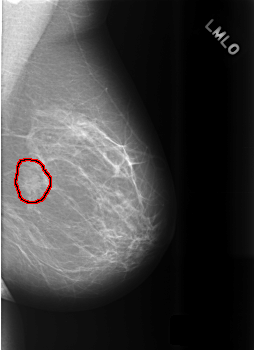

C_0469_1.LEFT_MLO

LEFT_MLO LINES 5592 PIXELS_PER_LINE 4064 BITS_PER_PIXEL 12 RESOLUTION 50 OVERLAY

FILE: C_0469_1.LEFT_MLO.OVERLAY

TOTAL_ABNORMALITIES 1

ABNORMALITY 1

LESION_TYPE MASS SHAPE IRREGULAR MARGINS SPICULATED

ASSESSMENT 3

SUBTLETY 5

PATHOLOGY BENIGN_WITHOUT_CALLBACK

TOTAL_OUTLINES 1

BOUNDARY